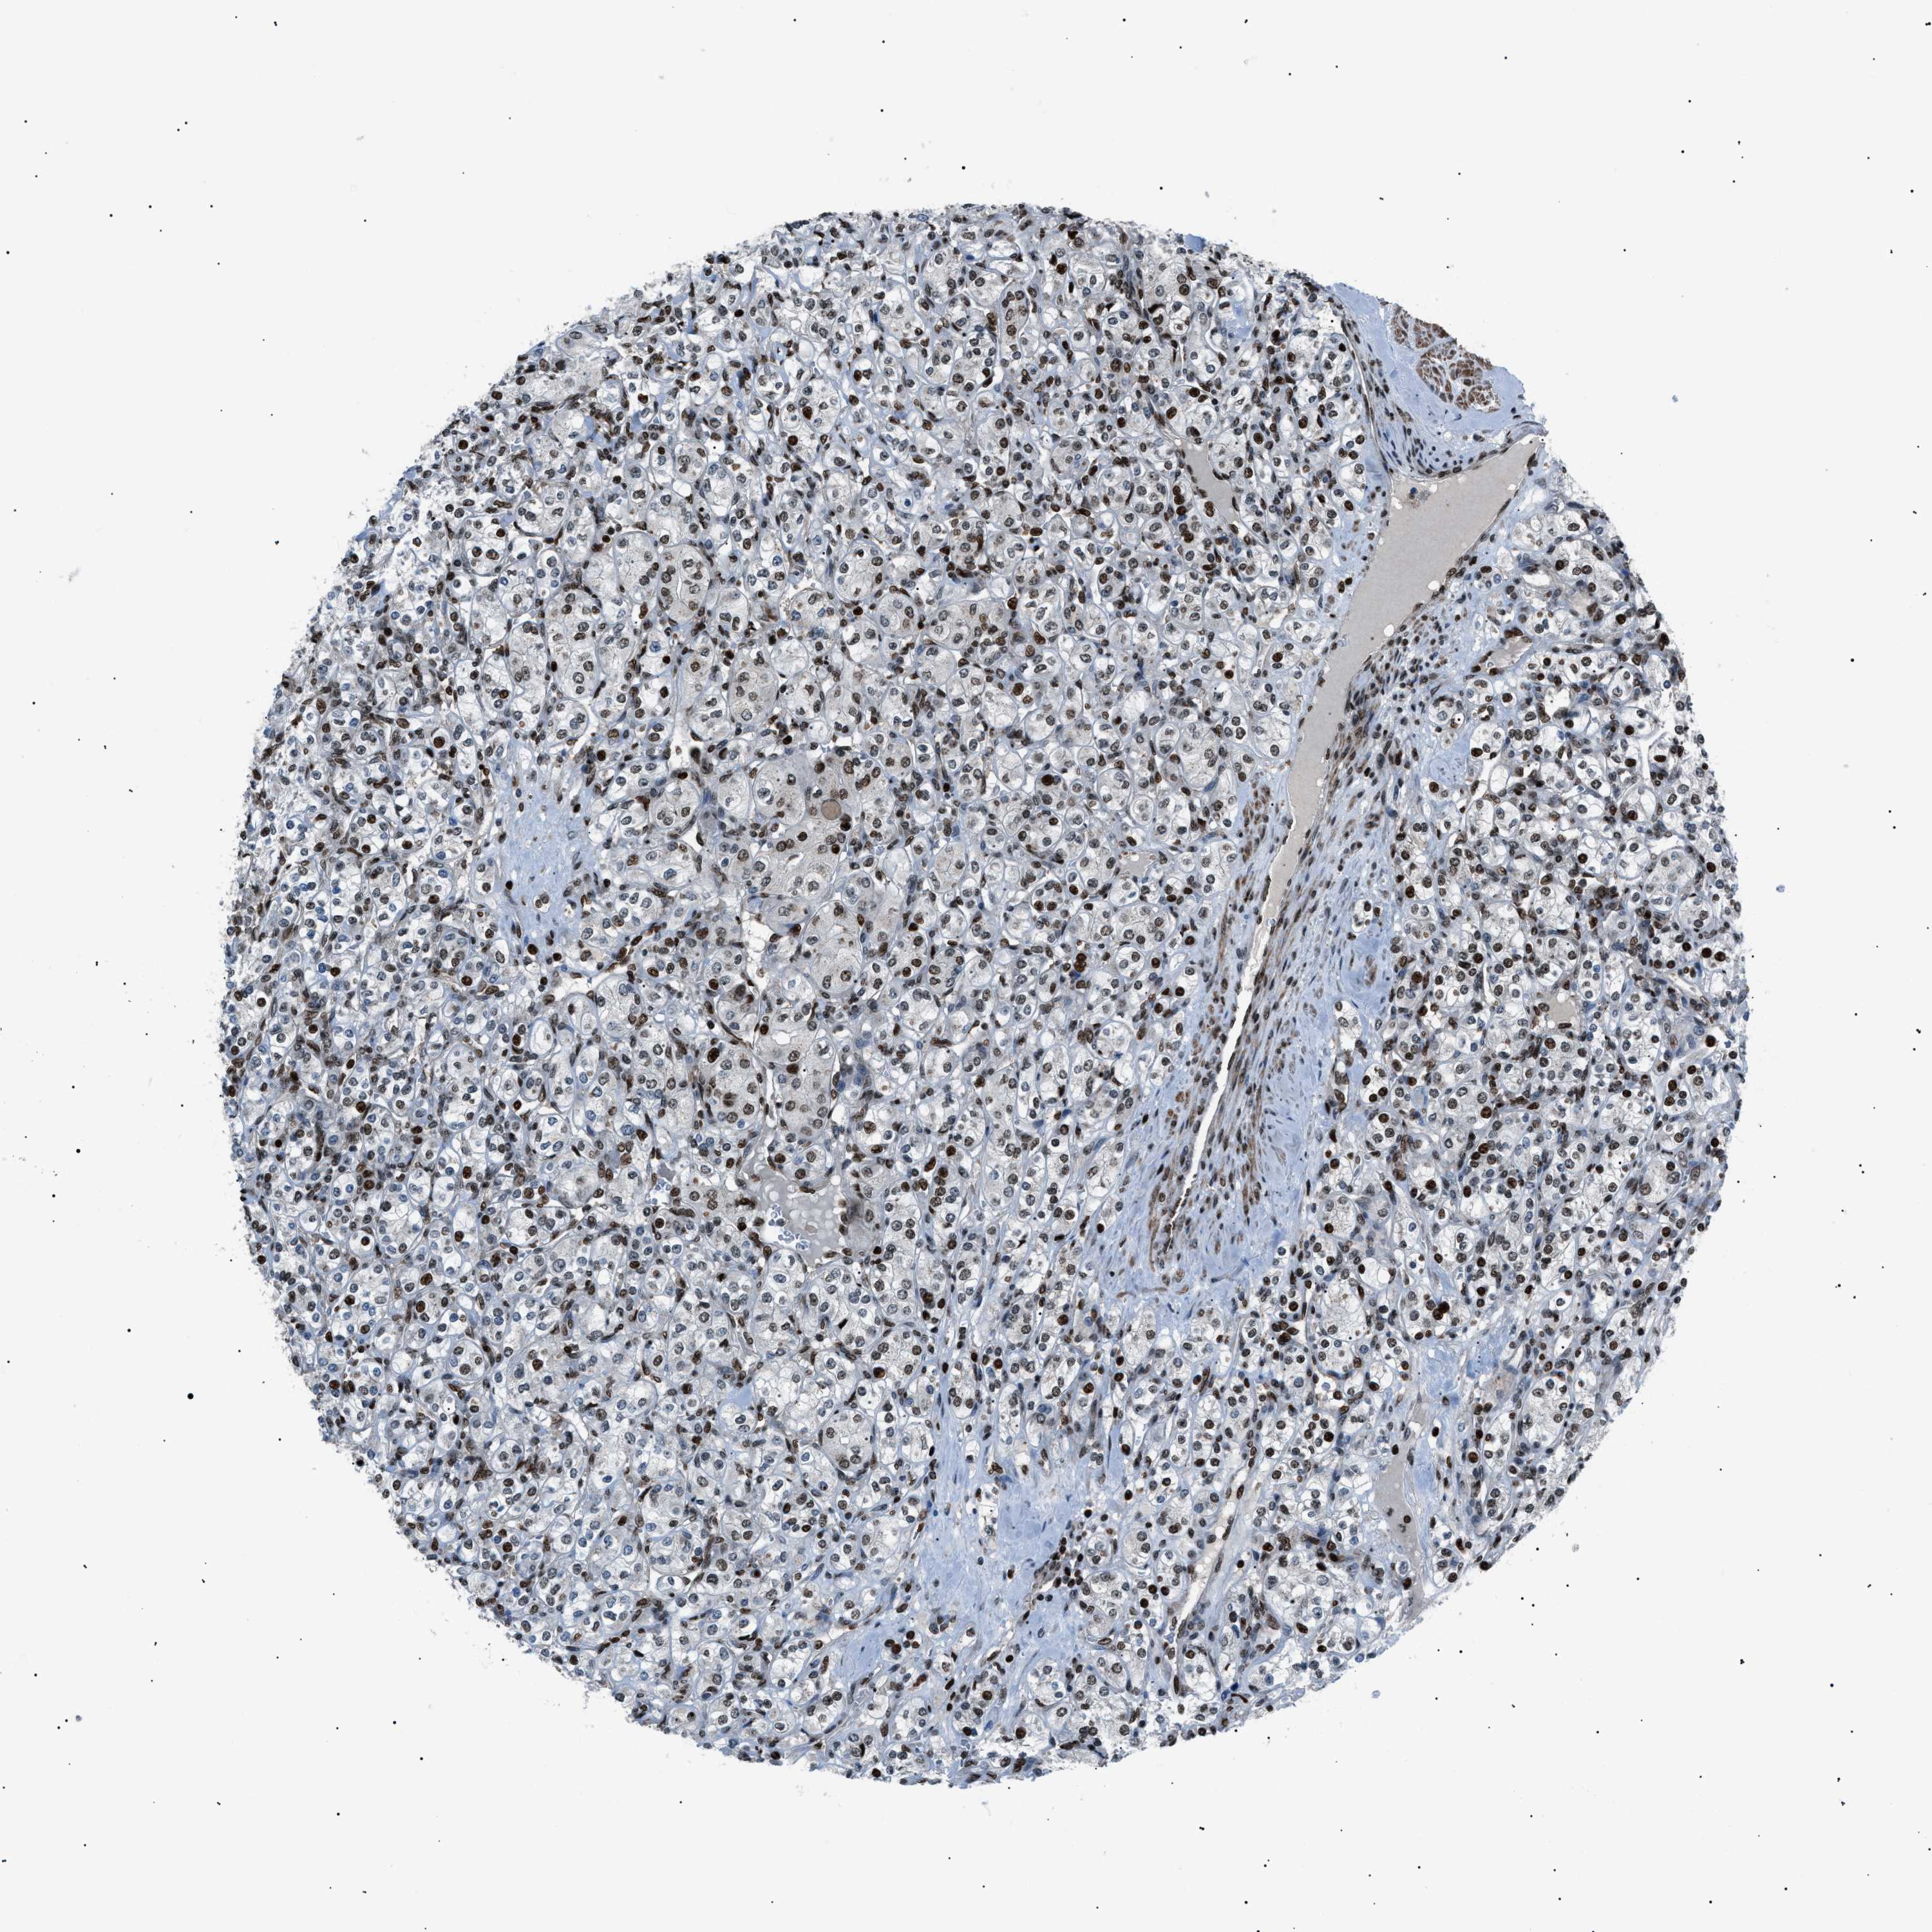

KIDNEY RENAL CLEAR CELL CARCINOMA (TCGA) - Interactive survival scatter ploti

The Survival Scatter plot shows the clinical status (i.e. dead or alive) for all individuals in the patient cohort, based on the same data that underlies the corresponding Kaplan-Meier plots. Patients that are alive at last time for follow-up are shown in blue and patients who have died during the study are shown in red.

The x-axis shows the expression levels (FPKM) of the investigated gene in the tumor tissue at the time of diagnosis. The y-axis shows the follow-up time after diagnosis (years). Both axes are complimented with kernel density curves demonstrating the data density over the axes. The top density plot shows the expression levels (FPKM) distribution among dead (red) and alive patients (blue). The right density plot shows the data density of the survived years of dead patients with high and low expression levels respectively, stratified using the cutoff indicated by the vertical dashed line through the Survival Scatter plot. This cutoff is automatically defined based on the FPKM cutoff that minimizes the p-score. The cutoff can be changed by dragging the vertical line or by entering a cutoff value in the square labeled "Current cut-off".

Under the Survival Scatter plot the p-score landscape (black curve; left axis) is shown together with dead median separation (red curve; right axis). Dead median separation is the difference in median mRNA expression between patients who have died with high and low expression, respectively. It is calculated as follows: median FPKM expression of dead patients with high expression - median FPKM expression of dead patients with low expression. This is intended to aid the user in visually exploring custom cutoffs and the associated p-scores and dead median separation.

Individual patient data is displayed and can be filtered by clicking on one or more of the category buttons on the top of the page. Categories describing expression level and patient information include: high, low, alive, dead, female, male and tumor stages. The scale of the x-axis can be toggled between linear and log-scale by clicking on the "x log" button. Mouse-over function shows TCGA ID, patient information and mRNA expression (FPKM) for each patient.

& Survival analysisi

Kaplan-Meier plots summarize results from analysis of correlation between mRNA expression level and patient survival. Patients were divided based on level of expression into one of the two groups "low" (under cut off) or "high" (over cut off). X-axis shows time for survival (years) and y-axis shows the probability of survival, where 1.0 corresponds to 100 percent.

PRKX is potential prognostic, high expression is favorable in Kidney Renal Clear Cell Carcinoma (TCGA)

: 9.13

Average pTPM 9.3

Number of samples 521